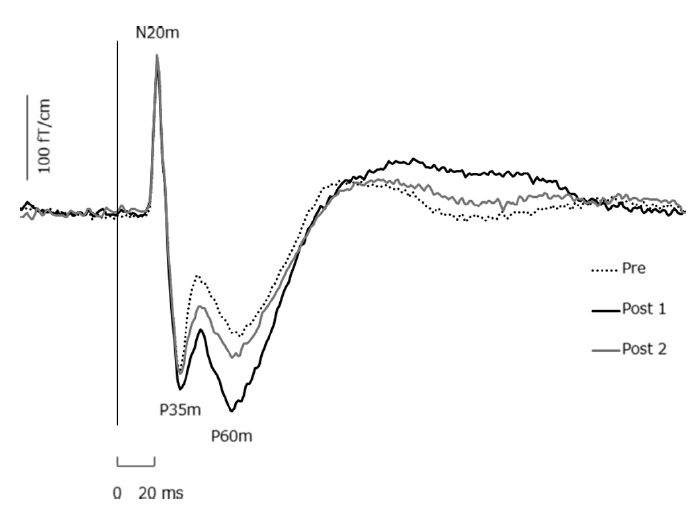

Kirimoto H, Tamaki H, Matsumoto T, Sugawara K, Suzuki M, Oyama M, Onishi H. Effect of transcranial static magnetic field stimulation over the sensorimotor cortex on somatosensory evoked potentials in humans. Brain Stim 2014 (in press)

Sugawara K, Onishi H, Yamashiro K, Kojima S, Miyaguchi S, Kirimoto H, Tsubaki A, Tamaki H, Shirozu H, Kameyama S. The effect of anodal transcranial direct current stimulation over the primary motor or somatosensory cortices on somatosensory evoked magnetic fields.Clin Neurophysiol. 2014 (in press)